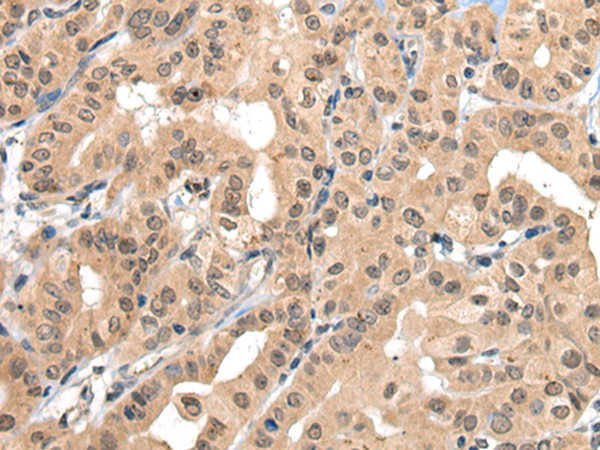

IHC positive control:

Human thyroid cancer and human colorectal cancer

IHC Recommend dilution:

30-150